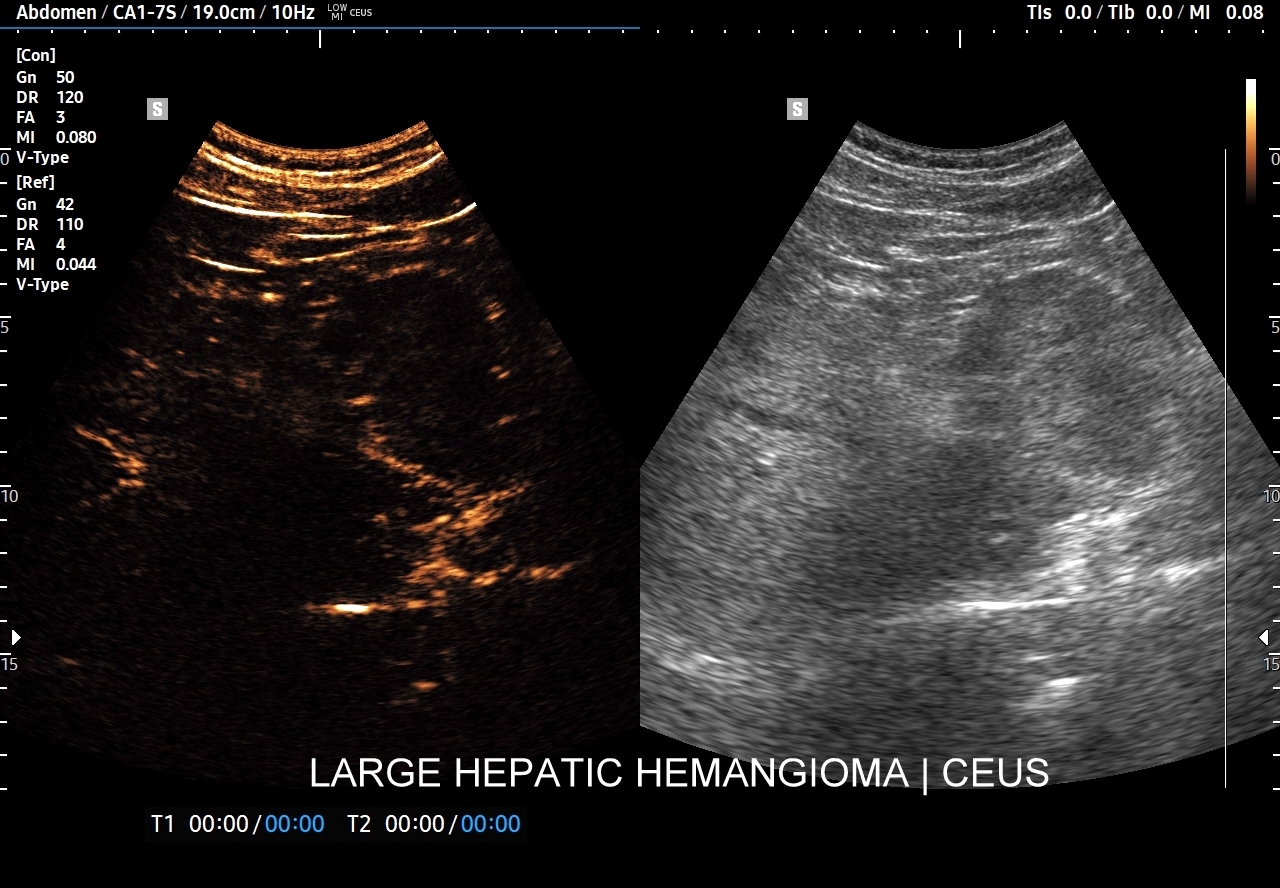

Najbardziej charakterystyczną cechą naczyniaka wątroby w badaniu CEUS jest jego wypełnianie w postaci guzkowej (ang. peripheral nodular enhancement) od obwodu ku centrum zmiany (ang. centripetal). Szybkość wypełniania bywa różnorodna, może być powolna lub szybka. W przypadku szybkiego wypełniania (tzw. flash-filling), w celu wykazania charakterystycznego centrypetalnego wypełniania niezbędna może być postprocessing’owa analiza poklatkowa zapisanego nagrania badania. W fazie późnej naczyniak wątroby pozostaje izowzmocniony lub hyperwzmocniony w stosunku do natywnego miąższu wątroby.

W przypadku dużych naczyniaków obszary, które uległy wykrzepianiu pozostają awaskularne przez wszystkie fazy badania CEUS, tj. nie wypełniają się kontrastem (nonenhancing). W przeciwieństwie do powyższego konstelacja, w której to w fazie wczesnej pojawia się wzmocnienie, a następnie w fazie wrotnej lub późnej ulega wypłukaniu (hypoenhancement) świadczy o cechach złośliwych diagnozowanej zmiany ogniskowej w wątrobie i wyklucza rozpoznanie naczyniaka.